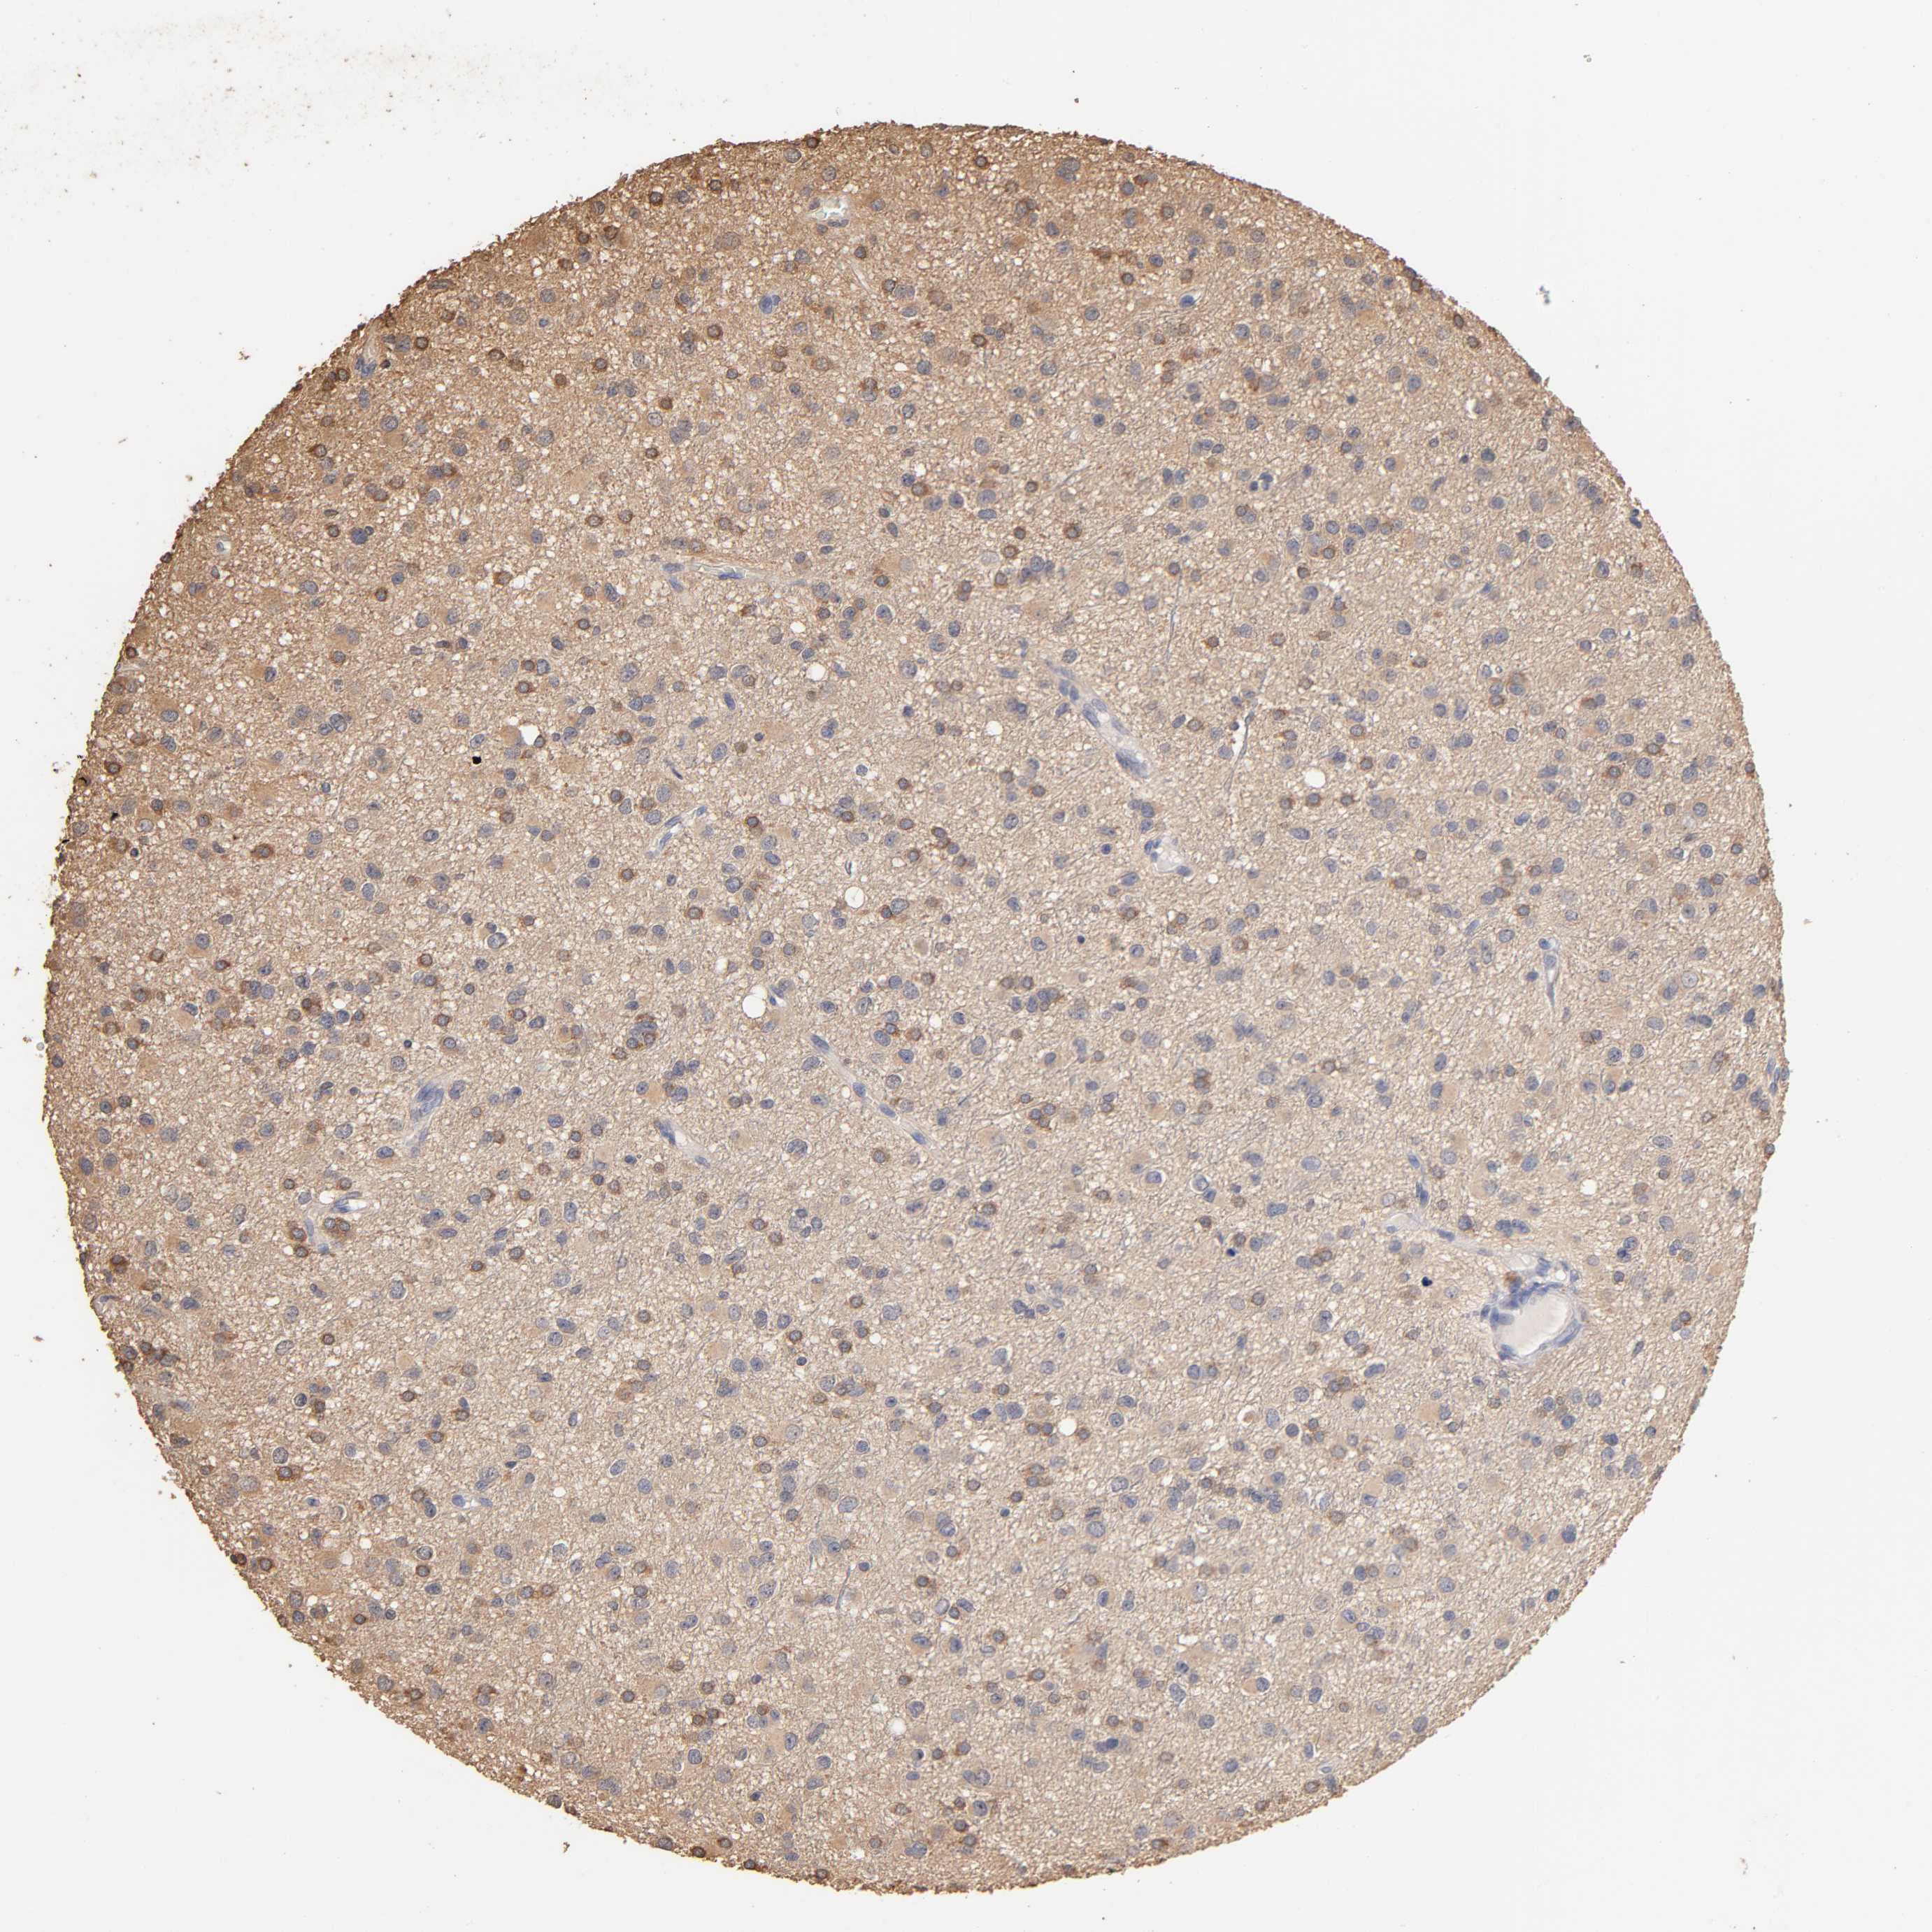

GLIOMA - Protein expressioni

A mouse-over function shows sample information and annotation data. Click on an image to view it in a full screen mode. Samples can be filtered based on level of antibody staining by selecting one or several of the following categories: high, medium, low and not detected. The assay and annotation is described here.

Note that samples used for immunohistochemistry by the Human Protein Atlas do not correspond to samples in the TCGA dataset.

Antibody stainingi

Antibody staining in the annotated cell types in the current human tissue is reported as not detected, low, medium, or high, based on conventional immunohistochemistry profiling in selected tissues. This score is based on the combination of the staining intensity and fraction of stained cells.

Each image is clickable and will lead to virtual microscopy that enables deeper exploration of all samples and also displays staining intensity scores, fraction scores and subcellular localization as well as patient and tissue information for each sample.

Antibody HPA003903

Antibody HPA072756

Antibody CAB026000

Staining

High

Medium

Low

Not detected

Intensity

Strong

Moderate

Weak

Negative

Quantity

>75%

75%-25%

<25%

None

Location

Nuclear

Cytoplasmic/membranous

Cytoplasmic/membranous,nuclear

Glioma, malignant, High grade

Glioma, malignant, NOS

Glioma, malignant, Low grade